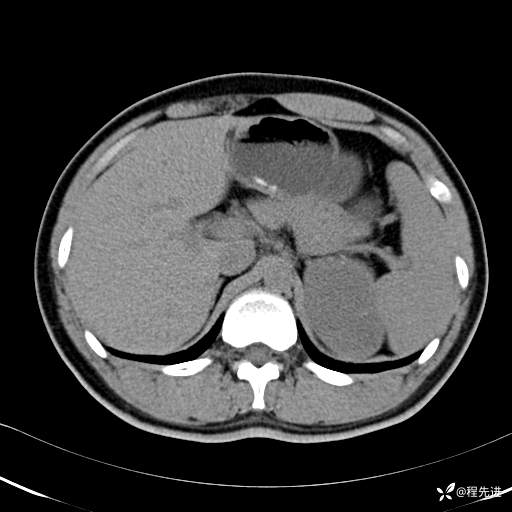

【腹盆】特别精彩病例|体检发现的左侧腹膜后占位期待您的精彩解读

患者年龄:25岁

简要病史:体检发现

CT平扫:(CT值:平扫,27HU,动脉期,27HU,门静脉期,31HU,平衡期,32HU)

CT增强:

动脉期:

门静脉期: